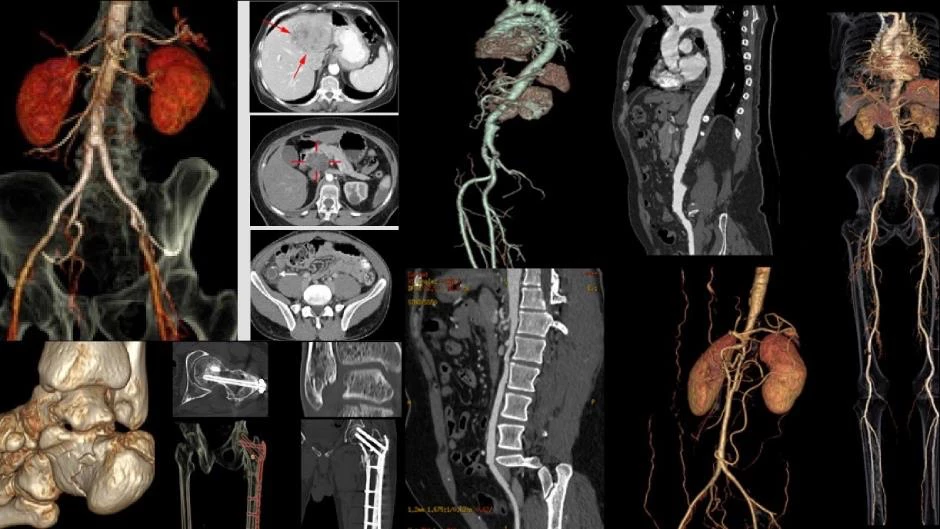

Tại hội nghị năm nay, Bernard tiếp tục công bố 2 nghiên cứu "Double Reading and Discrepancies in Diagnostic Imaging: A Cross-Sectional Study at Bernard Healthcare, Vietnam" (Tham vấn ý kiến thứ 2 và sự khác biệt trong chẩn đoán hình ảnh: Một nghiên cứu cắt ngang tại Bernard Healthcare và Bệnh viện Đại học Yamanashi) và "Body Fat, Lifestyle Habits and Their Association with Gastroesophageal Reflux Disease in Vietnamese Ningen Dock Clients" (Tỷ lệ mỡ cơ thể, thói quen lối sống và mối liên quan với bệnh GERD ở khách hàng Ningen Dock Bernard).

Cả hai nghiên cứu đều được hội đồng khoa học đánh giá cao nhờ giá trị thực tiễn. Nghiên cứu thứ nhất cung cấp dữ liệu về hiệu quả của phương pháp tham vấn ý kiến thứ hai trong chẩn đoán hình ảnh - vốn là một trong những vấn đề đang được quan tâm trong lĩnh vực hạn chế sai sót y khoa. Nghiên cứu thứ hai đưa ra mối liên hệ giữa lối sống, tỷ lệ mỡ cơ thể và bệnh trào ngược dạ dày - thực quản - một trong những căn bệnh tiêu hóa phổ biến, giúp định hướng chiến lược dự phòng bệnh cho đối tượng khách hàng Bernard cũng như cộng đồng.